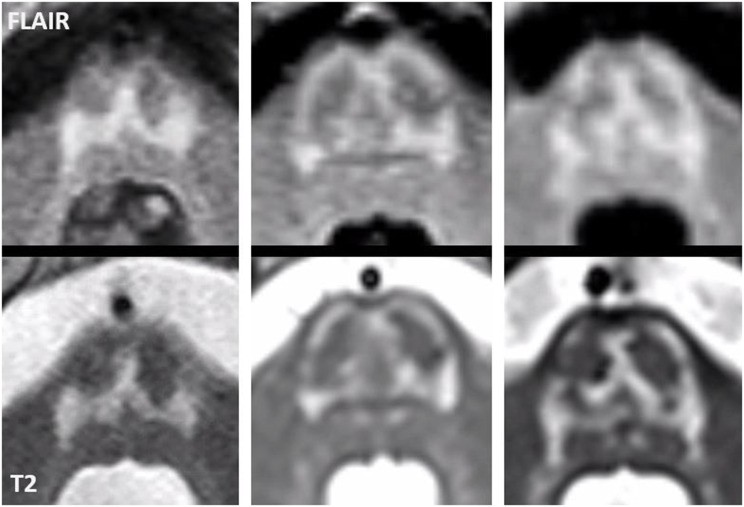

In all adult patients, the first MRI already showed characteristic abnormalities. The typical MRI pattern consisted of symmetric T2 hyperintense signal abnormalities in the thalami, midbrain and pons (Fig. 2). The thalami were affected in eight of the nine patients. The midbrain was affected in all nine adult patients, including T2 hyperintensity of the substantia nigra in all patients and superior colliculi in seven patients. The grey matter of the pons was selectively involved in eight patients, sparing the corticospinal tracts as well as the ascending sensory tracts. This created either a trident-like configuration or a closed omega (ɷ) (Fig. 3), which was noted in four and two patients, respectively.

We have performed a detailed analysis of the brain MRI abnormalities associated with AMACR deficiency. In the adult patients in our cohort the characteristic MRI pattern involved the pons, midbrain and thalami. Interestingly, we found that the structures involved in the brain stem are grey matter structures with sparing of the major white matter tracts, i.e., corticospinal tracts and ascending sensory tracts. This selective vulnerability is easier to appreciate by comparing MR images of patients with MR images of healthy adults acquired with a sequence optimized to discriminate brain stem nuclei [ref. 22]. On the FLAIR and T2-weighted images in most of our patients this grey matter pathology resulted in the pons in either a trident-like hyperintensity or a closed omega (ɷ). A trident-like abnormality in the pons can also be recognized in patients with osmotic demyelination syndrome [ref. 23], although in those cases it usually is more voluminous than in patients with an AMACR deficiency. Although MRI abnormalities in adults with AMACR deficiency have been described before [ref. 11], the pattern of selective grey matter vulnerability has not been appreciated previously. Recognition of this typical pattern facilitates prompt diagnosis. This is supported by the finding that all adults in our cohort showed characteristic MRI abnormalities at presentation and the majority was diagnosed after recognition of the typical pattern. The abnormalities involving the dentate nucleus, red nucleus and connecting dentatorubral tracts within the superior cerebellar peduncles, described earlier in a study by Haugarvoll et al. [ref. 11], are recognizable in part of our patient group. The signal changes in the dentate nucleus and superior cerebellar peduncles are generally less pronounced or more subtle than those in the pons, midbrain and thalamus. Since none of the children in our cohort showed MRI abnormalities at diagnosis or follow-up, it is unknown whether the neurological symptoms seen in the adult patients are preceded by MRI abnormalities and, if so, by how long. Also, we cannot rule out that the here reported children will have a different course of disease than the adults included in this cohort.